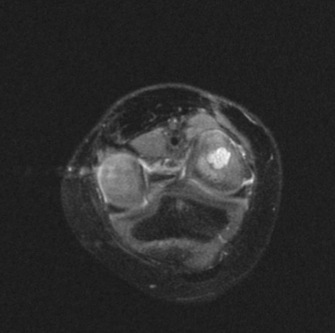

Figure 3 for case Staphylococcus osteomyelitis ( RID3715 )

Figure 3